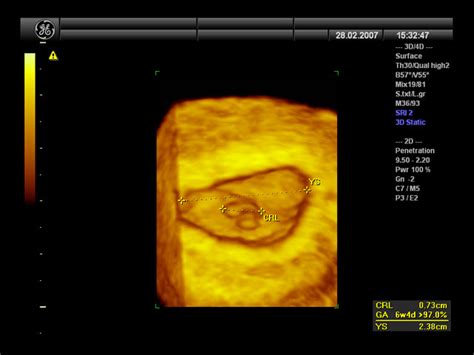

5. teden: Srček zarodka začne utripati, kar je pogosto mogoče zaznati z ultrazvočno preiskavo. Plod je velikosti sezamovega zrna. Začnejo se oblikovati drugi organi, kot so želodec, jetra in ledvice, ter sistemi organov, kot so žile, živčevje in prebavila. Ženske v tem času pogosto občutijo boleče in občutljive prsi, slabost in utrujenost. Naslednja struktura, ki postane vidna na ultrazvoku, je rumenjak, ki oskrbuje zarodek s hranili do razvoja posteljice. Rumenjak zraste do največ 6 mm.6. teden: V srčku se že formirajo štiri votline, rokice in nogice pa začnejo rasti. Zaradi rasti hormona nosečnosti, beta hCG, se slabost lahko stopnjuje. Ženske lahko postanejo razdražljive, se počutijo napihnjene in jim je pogosto slabo. Odmevi ploda, ki predstavljajo skupek plodovih celic, se prvič pokažejo na transvaginalnem ultrazvoku takoj po 6. tednu nosečnosti. Plod od 6. tedna dalje raste s hitrostjo približno 1 mm na dan.7. teden: Plod je velik približno 1 cm. Razvijajo se nos, jezik, ušesa, oblikujejo se prstki na rokah in nogah. Ena od treh nosečnic lahko v prvem trimesečju doživi krvavitev, ki je večinoma nenevarna. Vzroki so lahko ugnezditev ploda, hematom, grozeči splav ali krvavitev po spolnem odnosu. Zaradi rasti hormona progesterona je koža obraza lahko bolj sijoča, lasje pa gostejši.8. teden: Plod je dolg od 14 do 20 mm in tehta približno 1 g. Razvija se hrbtenica, kosti in črevesje; oblikujejo se kolena, komolci, zapestja in gležnji. Srčni utrip je lahko povišan, krvni pritisk pa pogosto znižan. Zaradi upočasnjene motilitete črevesa je zaprtost pogosta težava.9. teden: Od 9. tedna naprej zarodek postaja plod. Velik je približno 2,3 cm (kot zrno grozdja) in tehta 2 g. Prebavila in spolni organi so že formirani, vendar je še prezgodaj za določitev spola. Sluznica nosu je lahko nabrekla, pogosti sta utrujenost in vrtoglavica. Na podlagi izmerjene dolžine plodovega odmeva (CRL - Crown-Rump Length) se v zgodnji nosečnosti gestacijska starost določi z dodajanjem te dolžine k 6 tednom nosečnosti. CRL meritev je ponovljivo in najbolj natančno merilo gestacijske starosti.10. teden: Plod je velik 3,1 cm in tehta 4 g. Ledvice, jetra in pljuča že delujejo, vendar se bodo razvijali in dozorevali celotno nosečnost. Ločijo se prstki na nogah in pojavljajo se nohti. Zaradi rasti hormona beta hCG se poveča število lojnih žlez in izboljša prekrvavljenost kože, kar daje nosečnici značilen "nosečniški sij".11. teden: Plod je velikosti fige, dolg 4,1 cm in težak 7 g. Od 11. do 20. tedna se bo njegova teža povečala za 30-krat, dolžina pa za 3-krat. V pljuča plod vnaša majhne količine plodovnice, kar pomaga pri razvoju pljuč. Ušesa so se že razvila. Začnejo se ciklusi spanja na 5 do 10 minut. Spolni organi so že popolnoma razviti, vendar spola še ni mogoče določiti z ultrazvokom. Nosečnica lahko še vedno doživlja slabosti, vrtoglavico in zaprtje. Pridobitev teže v prvem trimesečju je lahko med 500 in 1000 g na mesec, nekatere nosečnice pa lahko zaradi slabosti tudi izgubijo nekaj kilogramov.12. teden: Plod je velikosti slive, dolg 5,4 cm in tehta 14 g. Plodovo srce deluje kot pri odraslem. Centralno živčevje se razvija in zori. Maternica je velikosti grenivke in telo nosečnice se počasi spreminja. Imuniteta pade, kar je naraven odgovor na nosečnost, saj bi sicer telo lahko napadlo "vsiljivca", ki raste v maternici. Zaradi tega se nosečnice z avtoimunskimi boleznimi pogosto počutijo bolje med nosečnostjo. Po 12. tednu se CRL meritev običajno nadomesti z drugimi merami.13. teden: Plod je velikosti breskve, dolg 7,4 cm in tehta do 23 g. Glavica še vedno predstavlja polovico dolžine ploda, vendar okončine hitro rastejo, tako da bo do 20. tedna velikost glavice le še tretjina telesa ploda. Jutranje slabosti pogosto pojenjajo, pojavi se lahko zgaga. Nosečnica običajno ob tej priložnosti novico sporoči družini in prijateljem.